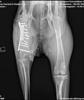

menschenorientiert, freundlich, anhänglich, aufmerksam, wachsam, gelehrig, zunächst misstrauisch bei fremden PersonenDoris ist eine vermutlich Anfang 2022 geborene, kastrierte Zentralasiatische Schäferhündin, die ausgesetzt gefunden und in das Tierheim unserer ungarischen Partnerorganisation gebracht wurde. Dort stellte sich heraus, dass sie einen schweren Unfall gehabt haben muss, denn sie hat rechts eine nicht versorgte und schlecht zusammengewachsene Oberschenkelfraktur.

Im Januar durfte Doris zu einer liebevollen Pflegestelle nach Österreich ziehen und hat seitdem die dringend benötigte Operation zur Stabilisierung des Knochens erhalten. Dank der großartigen Versorgung bei den Fachtierärzten Althangrund konnten wir die Kosten für diese lebensverändernde Operation von 8.000 Euro auf 5.000 Euro senken.

Die erste Operation verlief gut, und Doris’ Bein ist jetzt stabiler. Zur völligen Genesung benötigt sie nun jedoch eine Muskelansatz-OP, deren Kosten sich auf ca. € 2.300,– belaufen werden. Geld, das Animal Care Austria derzeit nicht aufbringen kann, da unsere Geldreserven erschöpft sind.